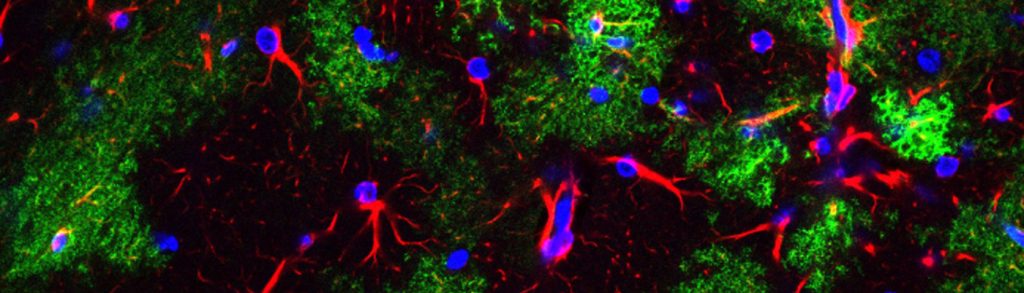

There is growing awareness that a common hallmark of neurological and psychiatric diseases is synaptic dysfunction. The Unit’s main focus is to evaluate how neurons, glial cells, and synapses are modulated, and how these processes are altered in disease states or restored by potential therapeutics. Current research addresses dysfunctions in various types of epilepsy, synaptic circuitry remodeling after stroke and seizures, synaptic reorganization following chronic drug abuse and/or depression, and functional alterations of neurons, glial cells, and synapses at the onset of neurodegenerative diseases such as amyotrophic lateral sclerosis, multiple sclerosis, and Alzheimer’s disease.

We aim to understand these dysfunctions at the synaptic and neuronal circuitry levels and to identify novel strategies that may pave the way for the discovery of more effective therapeutics.